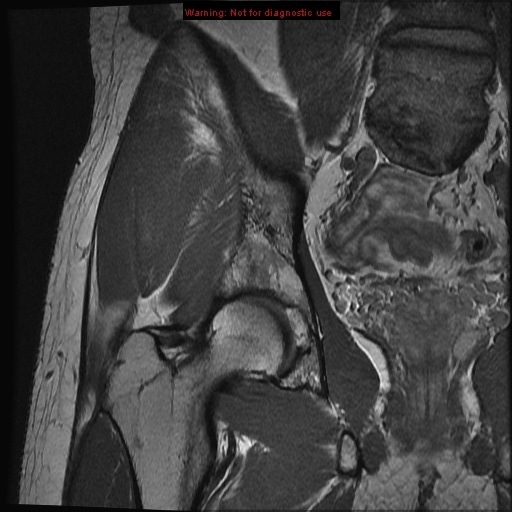

Hip Muscle Anatomy Radiology. The rectus femoris is one of the quadriceps of the thigh and arises at the anterior superior iliac spine. Foundations of Anatomy First Year Dental Head and Neck Anatomy Dent 545 Systems-based Anatomy Anat 403 for Undergraduate and Graduate Students.

Anatomy of the Hip. The Department of Radiology at UW is committed to making significant improvements in current and future healthcare and the well-being of patients through imaging research and development. Foundations of Anatomy First Year Dental Head and Neck Anatomy Dent 545 Systems-based Anatomy Anat 403 for Undergraduate and Graduate Students.

Horizontal M1-segment gives rise to the lateral lenticulostriate arteries which supply part of head and body of caudate globus pallidus putamen and the posterior limb of the internal capsule. This article considers the hip joint specifically however it is worth noting that the word hip is often used to refer more generally to the anatomical region around this joint. Understanding the anatomy of the hip is essential for diagnosing its pathology. The ulna long bone of the forearm humerus long bone of the arm from the shoulder and radius two large bones of the forearm are the three bones that make up the elbow4.